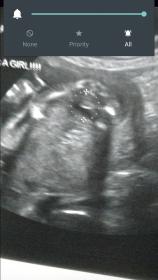

Went for ultrasound and was told girl but I'm just not seeing it. Sure I'm worrying for nothing. Can anyone tell me if they see girl?! Just looks like a ball and a line. Thanks yall! Just want more input! It's a potty shot 18 weeks 4 days.

Attachment 28270 zoomed in pic